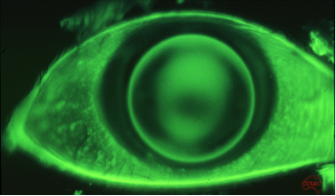

Causes Keratoconus has been associated with a variety of causes e.g.: Heredity Environment – more prevalent in hot, dry climates Atopic diseases with their associated conditions (asthma, hayfever, eczema, allergies) Oxidative stress – inability to eliminate/neutralize harmful free radicals which weakens the collagen and thins in cornea Endocrine system – strong association with puberty Eye rubbing – due to itchy eyes What is keratoconus? Prevalence How does it affect the patient? Treatment